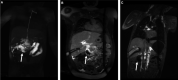

Background Protein-losing enteropathy (PLE) is a significant cause of morbidity and mortality in congenital heart disease patients with single ventricle physiology. Intrahepatic dynamic contrast-enhanced magnetic resonance lymphangiography (IH-DCMRL) is a novel diagnostic technique that may be useful in characterizing pathologic abdominal lymphatic flow in the congenital heart disease population and in diagnosing PLE. The objective of this study was to characterize differences in IH-DCMRL findings in patients with single ventricle congenital heart disease with and without PLE. Methods and Results This was a single-center retrospective study of IH-DCMRL findings and clinical data in 41 consecutive patients, 20 with PLE and 21 without PLE, with single ventricle physiology referred for lymphatic evaluation. There were 3 distinct duodenal imaging patterns by IH-DCMRL: (1) enhancement of the duodenal wall with leakage into the lumen, (2) enhancement of the duodenal wall without leakage into the lumen, and (3) no duodenal involvement. Patients with PLE were more likely to have duodenal involvement on IH-DCMRL than patients without PLE (P<0.001). Conclusions IH-DCMRL findings of lymphatic enhancement of the duodenal wall and leakage of lymph into the duodenal lumen are associated with PLE. IH-DCMRL is a useful new modality for characterizing pathologic abdominal lymphatic flow in PLE and might be useful as a risk-assessment tool for PLE in at-risk patients.